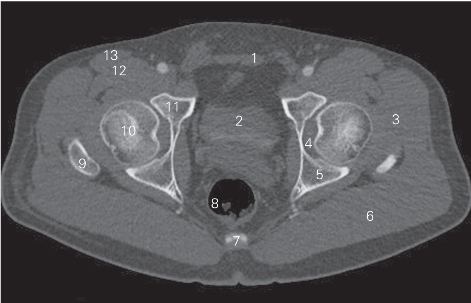

图5-2 经股骨头的横断层CT图像(骨窗)

1 腹直肌 rectus abdominis 2 膀胱 urinary bladder

3 臀中肌 gluteus medius 4 髋臼窝 acetabular fossa

5 坐骨体 body of ischium 6 臀大肌 gluteus maximus

7 尾骨 coccyx 8 直肠 rectum

9 大转子 greater trochanter 10 股骨头 femoral head

11 耻骨体 body of pubis 12 髂腰肌 iliopsoas

13 缝匠肌 sartorius